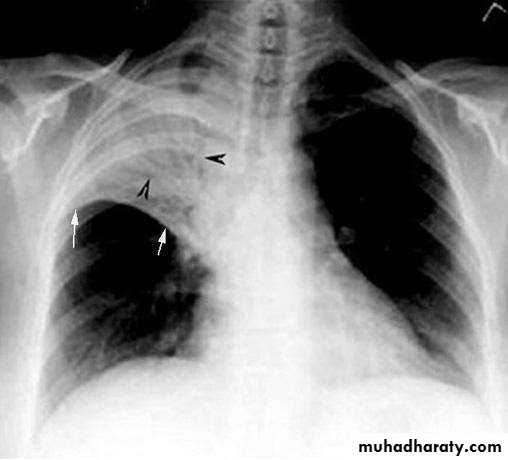

Chest X-ray and UltrasoundLobar pneumonia

• Patchy opacification ,consolidation.

• Air bronchogram (air-filled bronchi appear lucent against

consolidated lung tissue)

• X Ray

• Homogenous opacity with air bronchogram

• LOBAR PNEUMONIA

• Peripheral airspace consolidation pneumonia• Without prominent involvement of the bronchial tree

• RUL Consolidation

• RML Consolidation

• RLL Consolidation